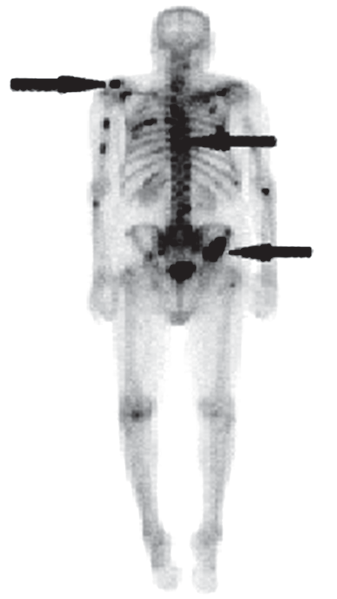

Na scyntygramie kości strzałkami oznaczono ogniska

A. zmian zwyrodnieniowych.

B. przerzutów nowotworowych.

C. stanów zapalnych.

D. osteoporozy.